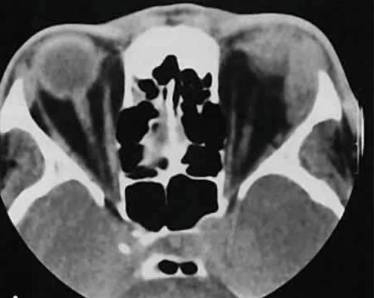

При пальпации шеи отмечается острая боль, мышцы уплотнены, может присоединяться покраснение и гиперемия. Для уточнения характера воспалительного процесса и его возбудителя производят анализ крови из пальца на стерильность и химический состав. Дополнительные методы исследования:

- Электромиография – показывает степень поражения нервных волокон, проводимость которых регулирует способность мышцы сокращаться.

- УЗИ мышц – помогает определить степень выраженности воспалительного процесса в шее.

- Рентгенография – помогает исключить вероятность развития патологий костной ткани.